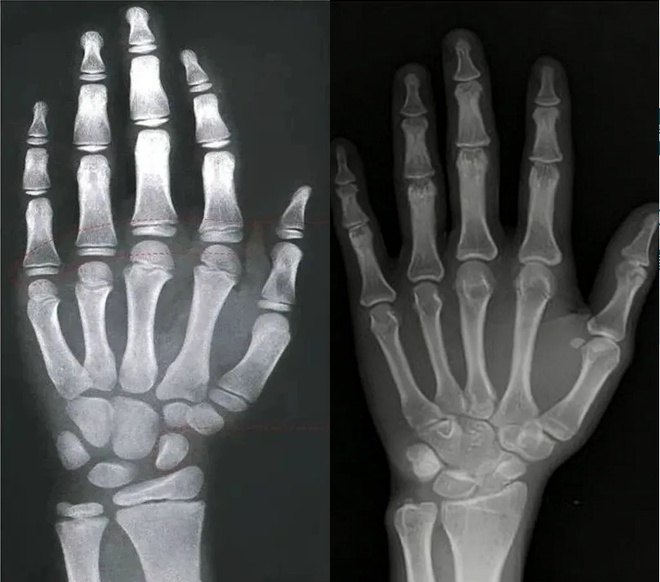

| Hình ảnh chụp X-quang cổ tay trái: các sụn đầu xương chưa đóng, trẻ vẫn còn tiềm năng phát triển (ảnh trái) và các sụn đầu xương đã đóng, chiều cao về cơ bản đã cố định (ảnh phải). Ảnh: QQ News. |

Cách chính xác nhất để xác định điều này là chụp X-quang cổ tay trái để quan sát tình trạng đóng sụn đầu xương.

Nếu phim X-quang cho thấy các sụn đầu xương chưa đóng lại, điều đó cho thấy trẻ vẫn còn tiềm năng phát triển; nếu chúng đã đóng hoàn toàn, chiều cao về cơ bản đã được cố định. Ngay cả khi trẻ thực sự còn nhỏ tuổi, nếu tuổi xương của trẻ đã phát triển và gần đóng sụn đầu xương, tiềm năng phát triển của trẻ sẽ bị hạn chế.

Bản chất của tăng trưởng chiều cao là sự phân chia và cốt hóa liên tục của các tế bào sụn ở đầu xương dài (như xương đùi và xương chày). Sụn này xuất hiện dưới dạng một “đường” mờ trên phim X-quang, đó chính là đường sụn đầu xương. Khi đường sụn đầu xương cốt hóa hoàn toàn và đóng lại, sự tăng trưởng chiều cao về cơ bản sẽ dừng lại.